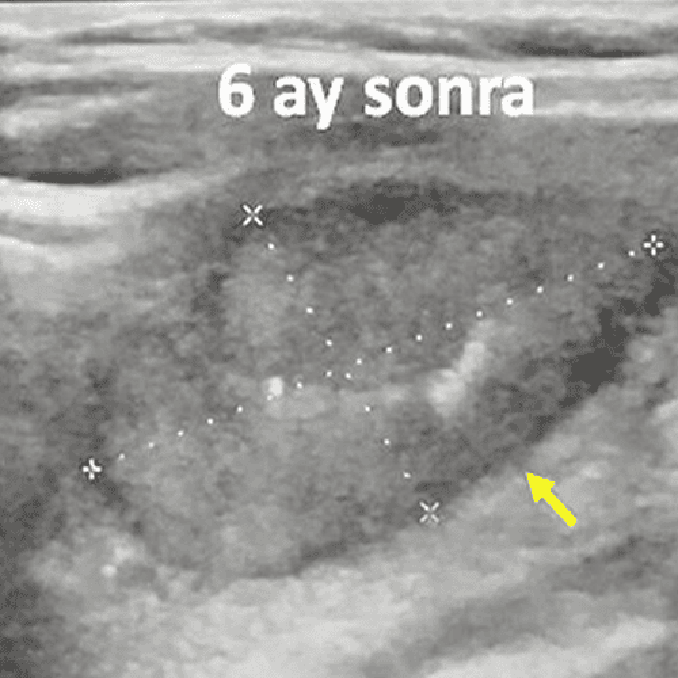

Sol tiroid lobunda 7 cm iyi huylu solid nodülü olan 48 yaşındaki erkek hastamıza embolizasyon tedavisi uygulandı. Altı ay sonra, nodülün hacmi % 80 oranında azalmış ve hastanın boynunun görünümü normale dönmüştür.